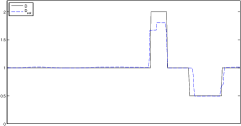

The data (see Figures 1 and 2) was generated in the diffusion model (1.2) using self-written (linear-basis) finite element code in MATLAB. For both examples, we took and used a uniform boundary condition . The simulated data were generated on a -grid and then down-sampled (by averaging) to to avoid inverse crime. After that, Gaussian noise with different intensities (standard deviations of and of the average signal value ) was added to the data.

The edge detector is used to detect jumps in the derivatives of the data up to second order (to obtain an initial estimate of the parameter jump set ). Since this process is highly sensitive with respect to noise, we varied the edge detection procedure subject to the amount of noise in the data. In the noise-free examples, we estimated the jumps of all three functions , that is, jumps of derivatives of up to second order. We restricted the jump estimation to for the low-noise examples (i.e., jumps of derivatives up to first order) and in the high-noise examples (only jumps in the data itself).

Reconstruction results and error profiles at different noise levels can be seen in Figures 3 and 4. In both examples, the noise-free reconstructions are very accurate and contain mostly smoothing error. In the low-noise reconstructions, due to the fact that more regularization is necessary, some of the parameter variation is underestimated. In the high-noise examples, most detail in is lost since a lot of regularization is required to get reasonable results. The fine detail in can, however, still be recovered very accurately in both examples.